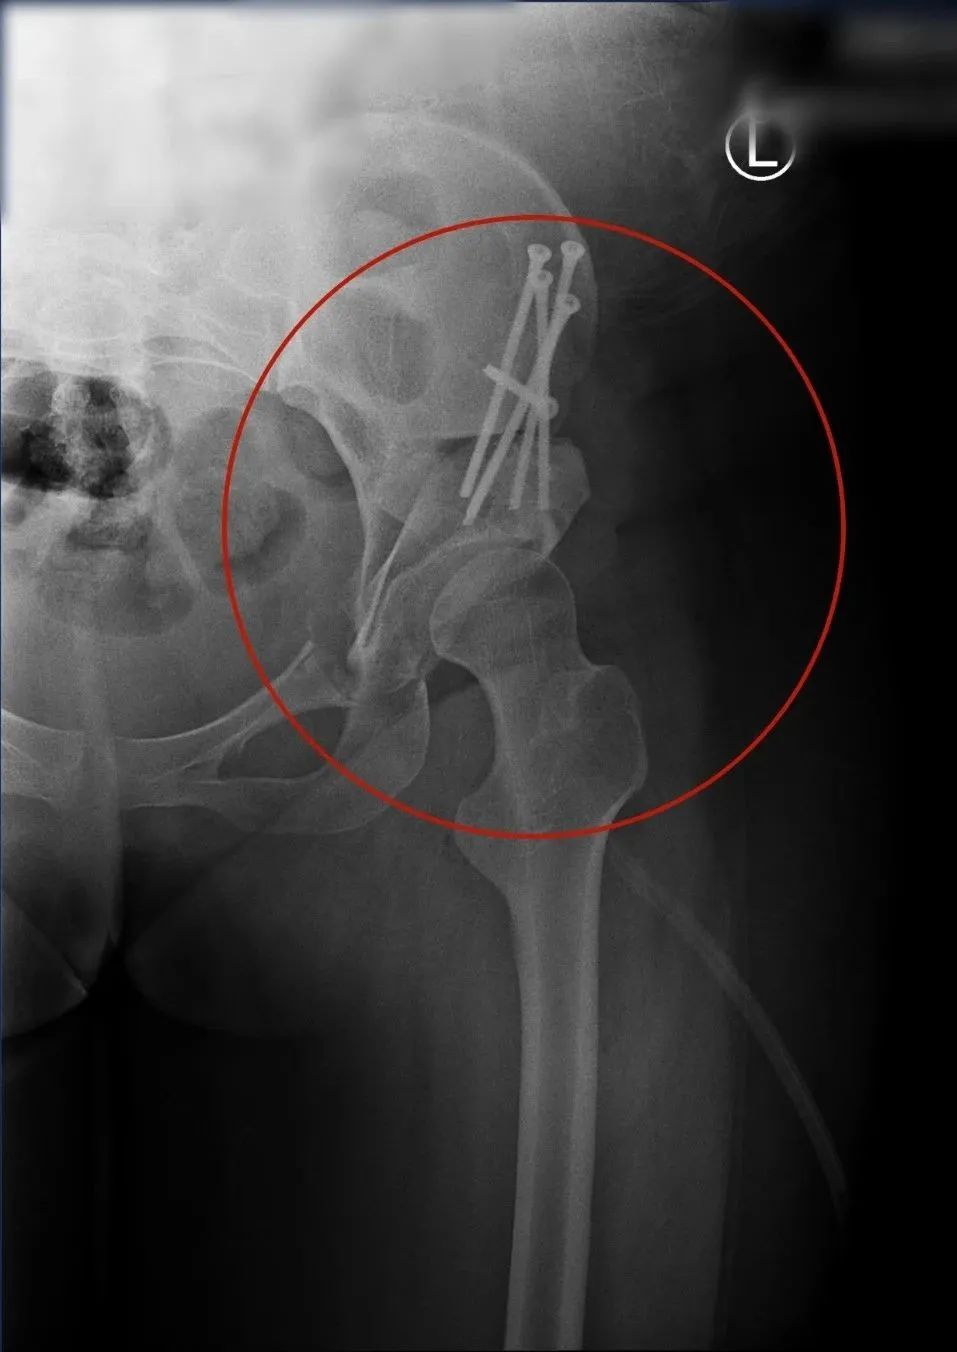

通过检查的结果,可以看出:

左侧的股骨头向上过度偏移

基本不在髋臼内

这也导致了左下肢短缩了3.3cm

属于相对严重的类型

幸运的是还有保髋的条件

发育正常的

髋关节

14岁男孩的

保髋治疗后的

术中,通过髋臼周围截骨术

让髋臼完全覆盖在了股骨头上

等骨骼愈合后,髋部的疼痛就没有了

双下肢也会一样长、还可以自由行走